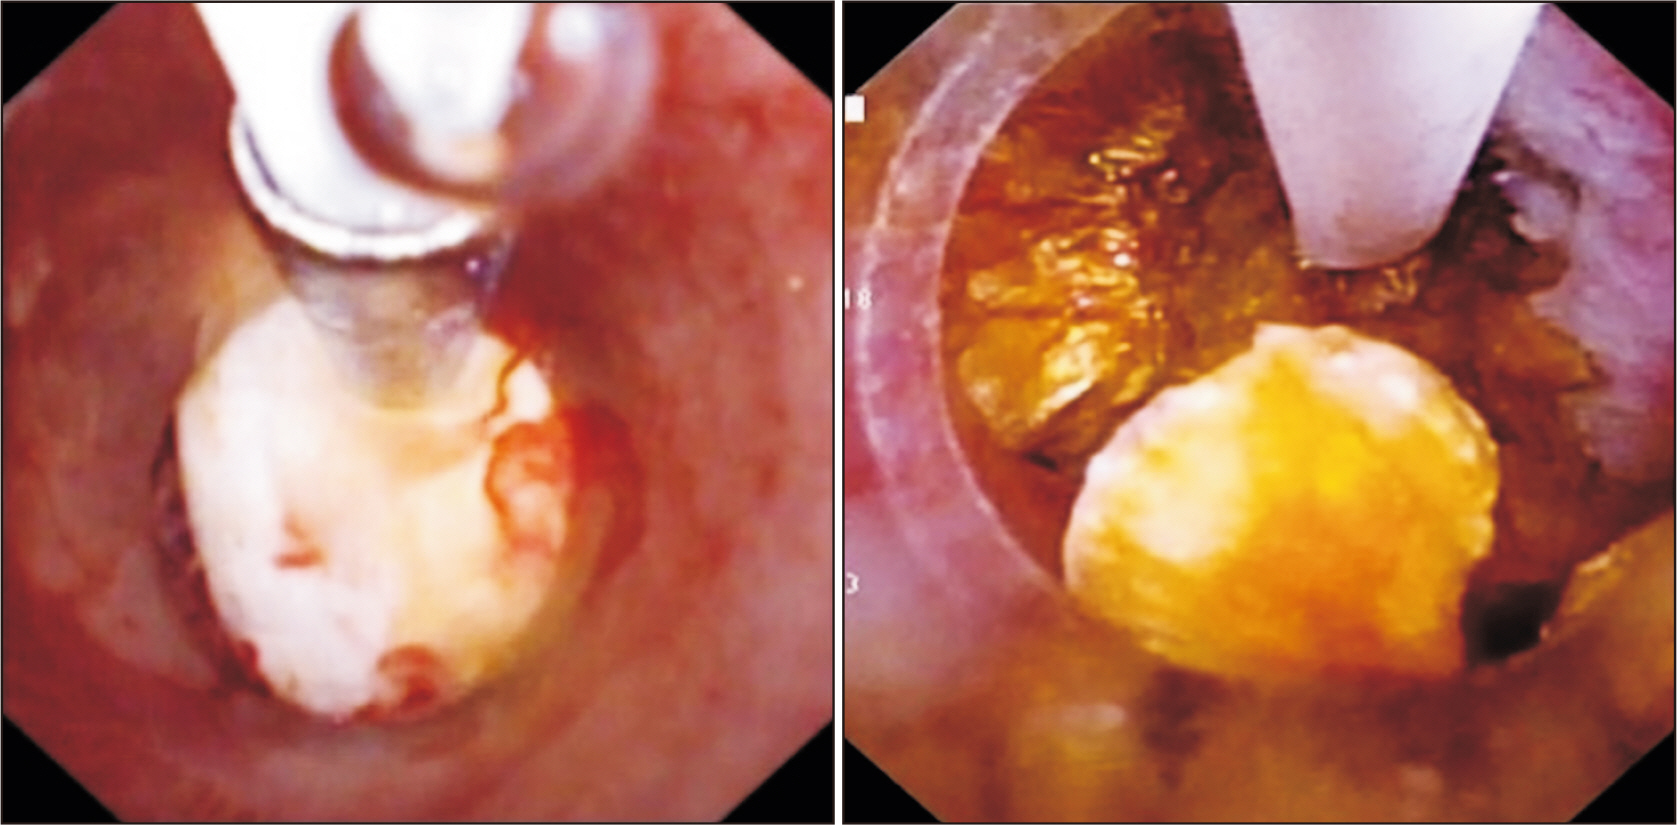

- Laparoscopic subtotal cholecystectomy (LSC) has been a safe and viable alternative to conversion to laparotomy in cases of severe cholecystitis. The objective of this study is to determine the utility of intraoperative choledochoscopy in LSC for the exploration of the gallbladder, cyst duct, and subsequent stone clearance of the cystic duct in cases of severe cholecystitis. A total of 72 patients diagnosed with severe cholecystitis received choledochoscopy-assisted laparoscopic subtotal cholecystectomy (CALSC). A choledochoscopy was performed to explore the gallbladder cavity and/or cystic duct, and to extract stones using a range of techniques. The clinical records, including the operative records and outcomes, were subjected to analysis. No LSC was converted to open surgery, and no bile duct or vascular injuries were sustained. All stones within the cystic duct were removed by a combination of techniques, including high-frequency needle knife electrotomy, basket, and electrohydraulic lithotripsy. A follow-up examination revealed the absence of residual bile duct stones, with the exception of one common bile duct stone, which was extracted via endoscopic retrograde cholangiopancreatography. In certain special cases, CALSC may prove to be an efficacious treatment for the management of severe cholecystitis. This technique allows for optimal comprehension of the situation within the gallbladder cavity and cystic duct, facilitating the removal of stones from the cystic duct and reducing the residue of the non-functional gallbladder remnant.

Figure